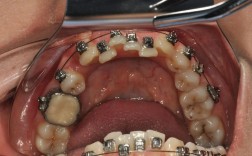

正畸治疗中,带环(也称为“牙带环”或“矫治器带环”)是固定矫治技术的重要组成部分,主要用于后牙(如磨牙)的固位,为后续的弓丝、托槽等附件提供稳定的支撑平台,带环的选择与佩戴是否合适,直接影响矫治力的有效传递、治疗效率及患者舒适度,本文将从带环的类型、型号选择依据、佩戴步骤及注意事项等方面详细说明,帮助读者全面了解正畸带环型号的选择与应用。

带环型号选择的操作步骤

初选型号与试戴

- 根据测量数据参考标准表初选带环型号,用带环试戴器(或手指)将带环套入模型牙齿,检查:

- 就位性:带环能否顺利滑入牙冠,无卡顿;若无法就位,需减小型号或调整带环边缘。

- 密合度:带环边缘与牙颈缘是否贴合,无明显缝隙(缝隙>0.5mm可能导致粘接失败);若缝隙过大,需更换更贴合的型号或定制带环。

- 牙龈刺激:带环边缘是否压迫牙龈模型,若牙龈被顶起,需减小高度或修整边缘。